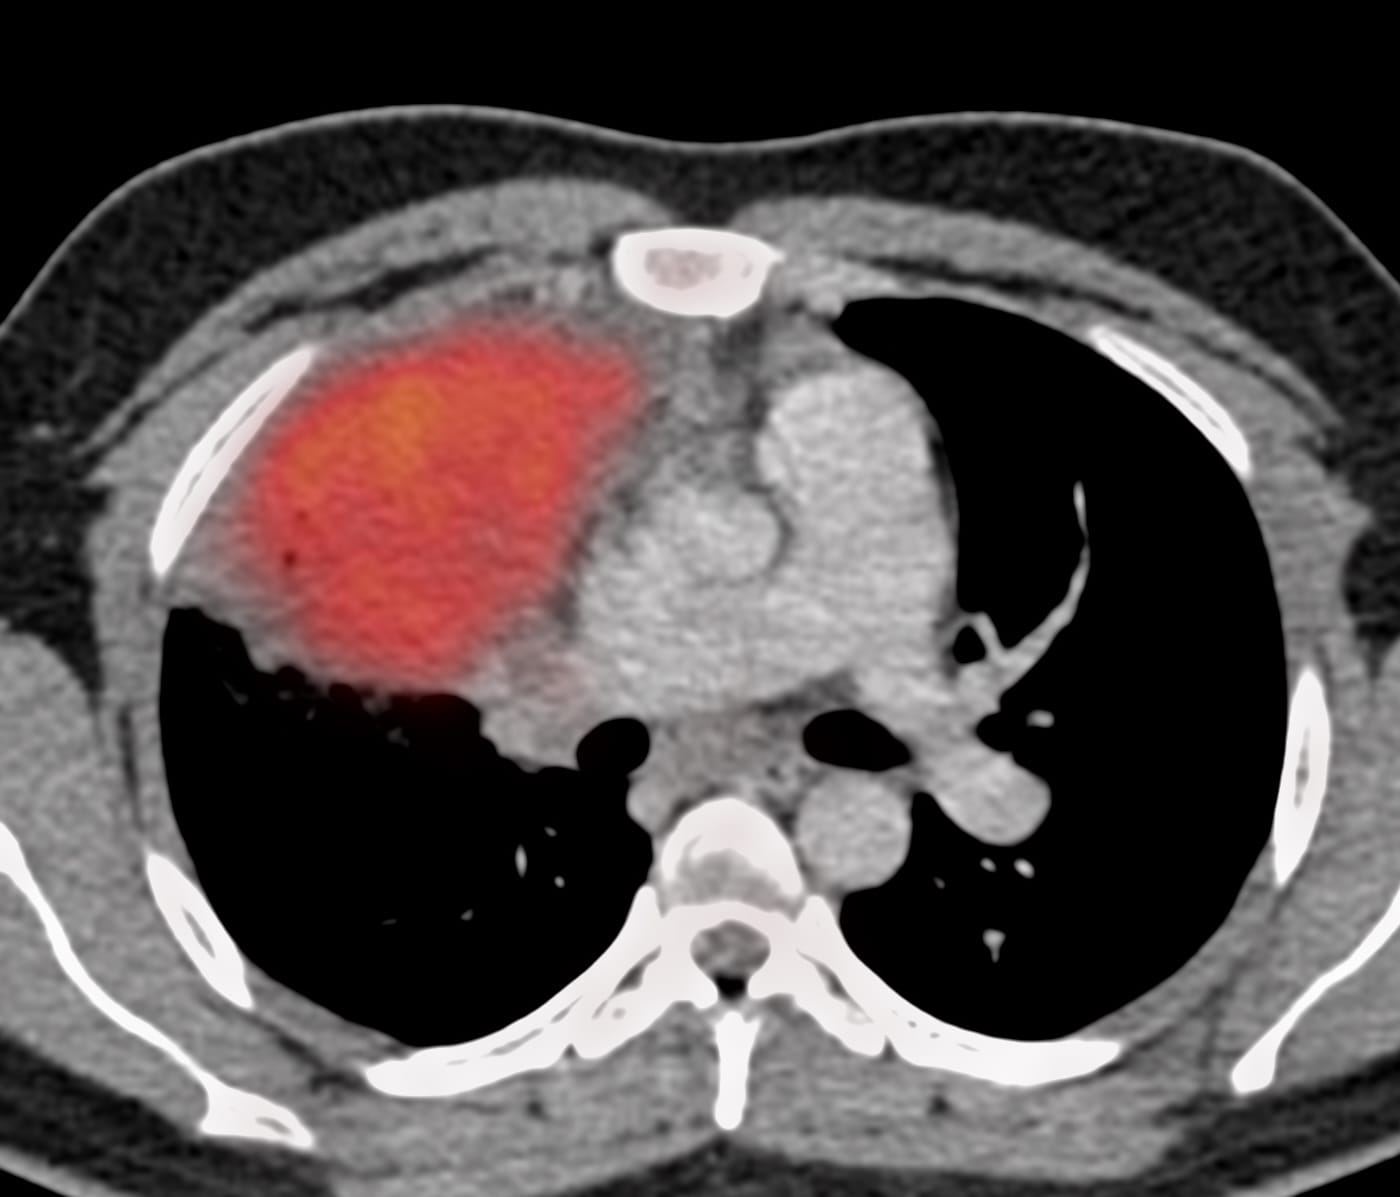

Case 14: 24-years old with fever and a non-resolving right upper lobe mass-like consolidation